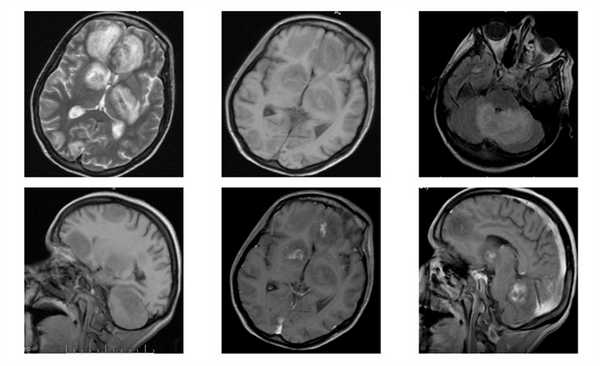

МРТ головного мозга. Аксиальная Т2-взвешенная МРТ. Расширение борозд и диффузные очаги.

Прогрессирование атрофии при прослеживании МРТ головного мозга в динамике происходит очень быстро.

МРТ головного мозга. Т2-взвешенные аксиальные МРТ типа FLAIR. Динамика очагов за полгода.

МРТ картина:

относительно симметричные диффузные или мультифокальные гиперинтенсивные изменения белого вещества в перивентрикулярной области и семиовальном центре с неровными краями, без масс-эффекта, не накапливающие контраст, либо более мелкие асимметричные очаги в белом веществе и базальных ядрах.

а-аксиальная КТ головного мозга

б,в,г -аксиальные МРТ в режимах Т2, Т1

аксиальная Т1 с контрастным усилением